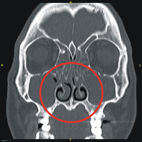

鄭先生是35歲男性,本身無特殊慢性疾病,近年來因為長年聞不到味道,合併有鼻塞情況來本院門診求診,經鼻咽內視鏡診察後發現雙側鼻腔內有鼻息肉(如:圖一),同時合併有膿鼻涕及鼻涕倒流情況(如:圖二)。電腦斷層檢查亦發現兩側鼻竇均有嚴重鼻息肉以及蓄膿情況 (如:圖三),由於過去數月在診所接受藥物治療效果不彰,因此經醫師建議接受電磁導航鼻竇內視鏡手術治療。

圖三、電腦斷層檢查顯示雙側嚴重鼻息肉及鼻蓄膿(紅色圈圈處)